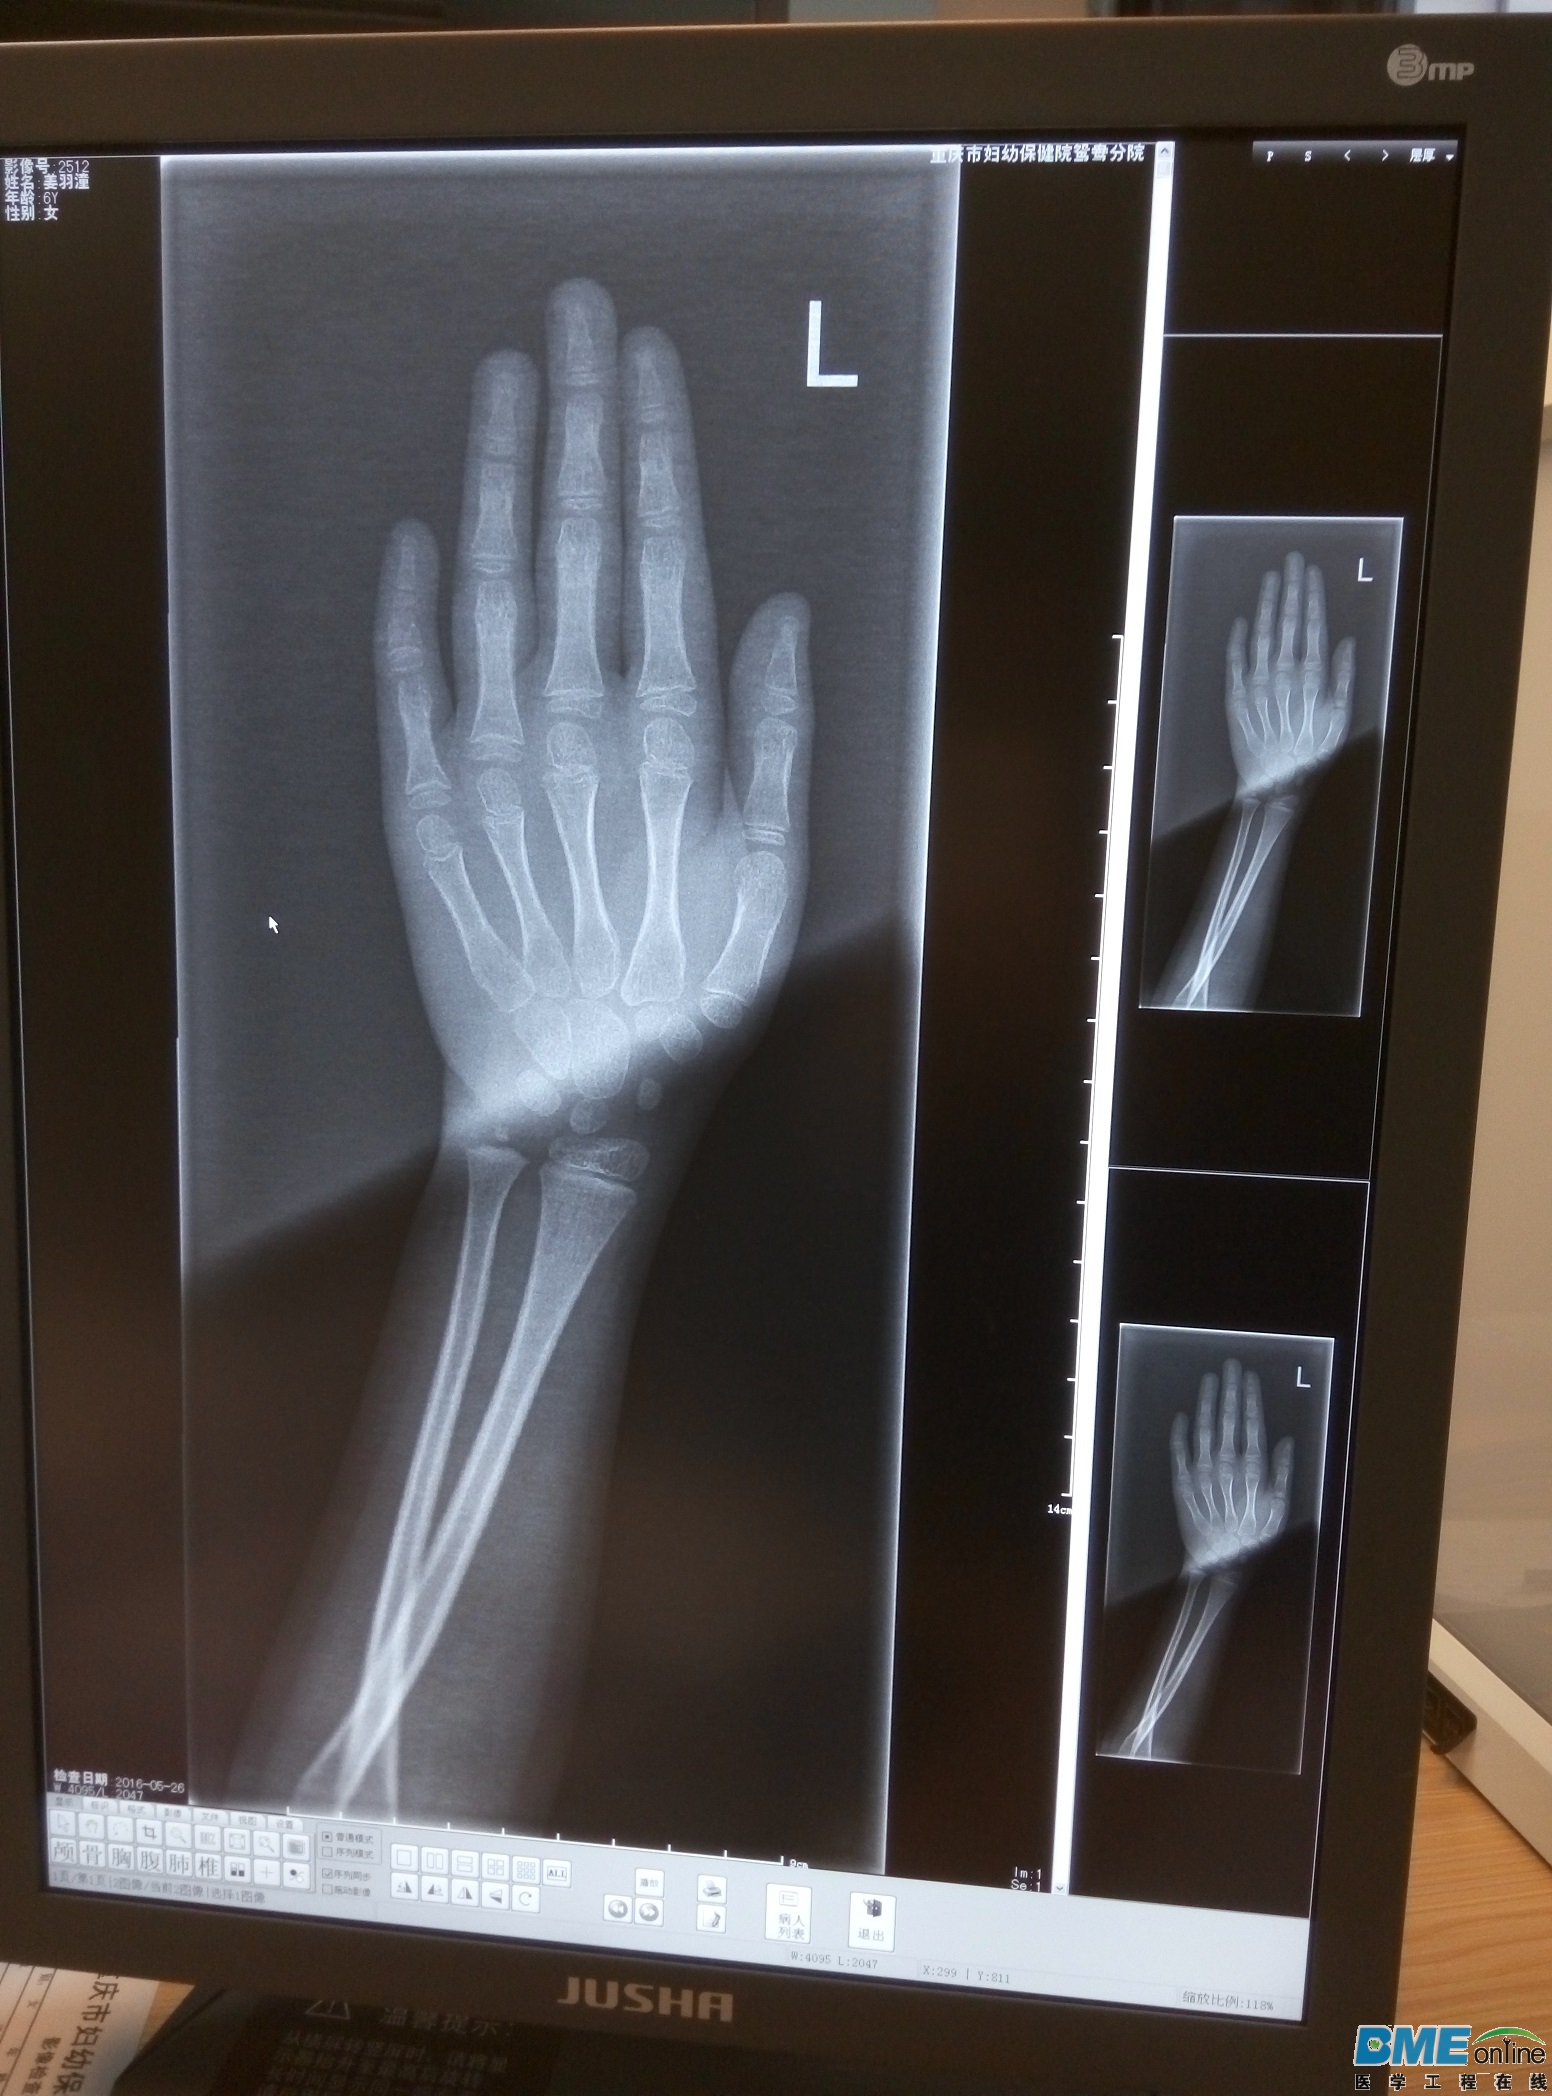

设备为飞利浦X射线系统,型号:Essenta DR Compact,出现拍片结果对比度不一致,如图,求助自己能解决不

已经解决了,做了探测器校准,图像好了些,后面拆开平板,发现里面有灰尘和水雾,估计是这段时间雨季潮湿,清洁处理后就正常了

感觉像阴阳片,训球管和探测器校准做了吗?